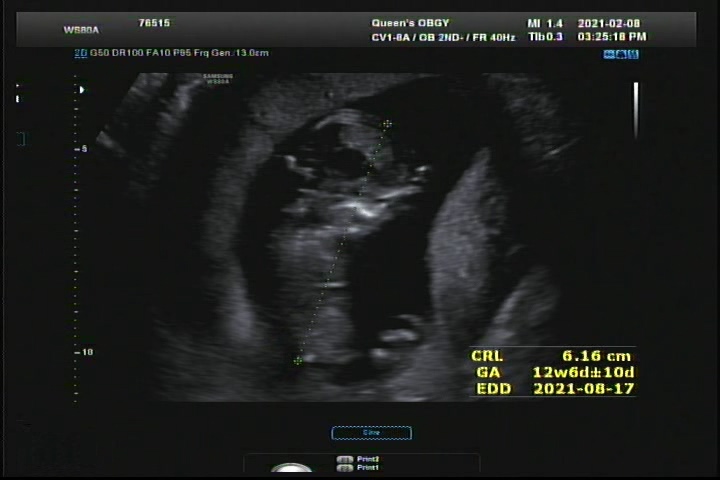

임신 12주차 1차 기형아검사 목투명대 측정 / 천안 산후조리원 예약

1차 기형아검사 시기 11주 ~ 13주에 하는 검사로 피검사, 초음파로 아기 목 투명대검사(NT)를 진행한다. ...